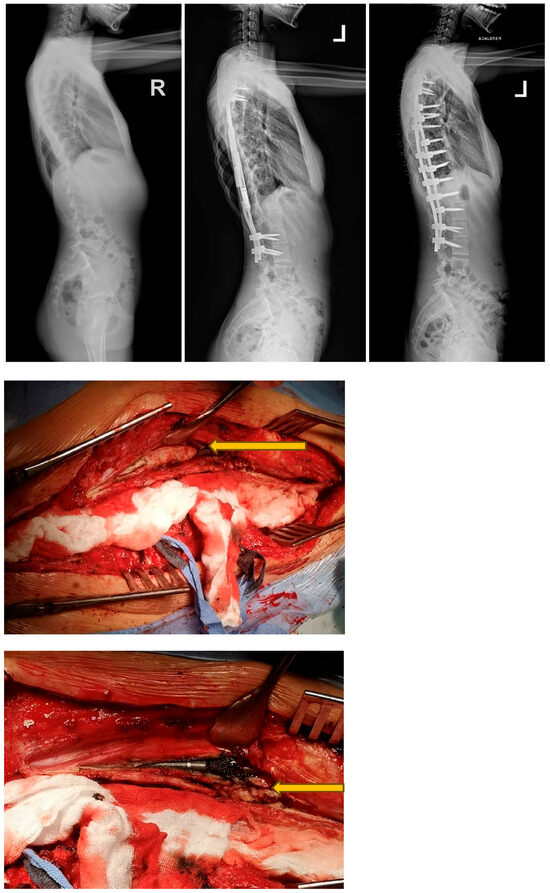

2.3. Surgical Technique and Postoperative Use of MCGRs